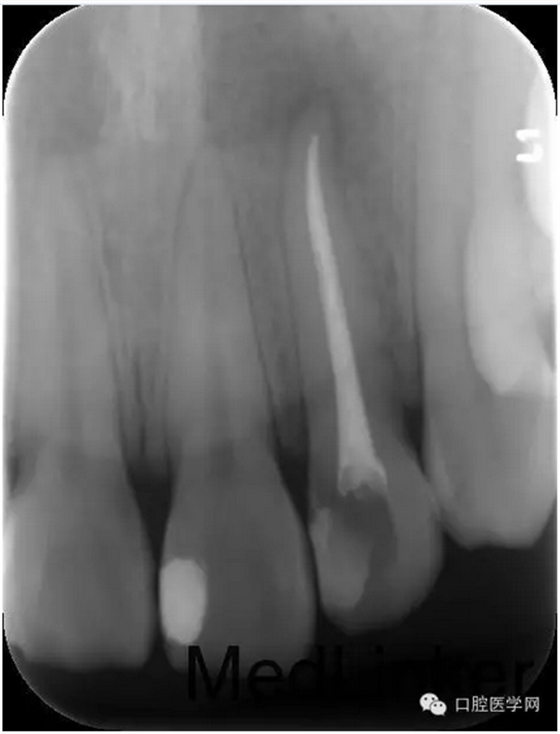

第三次:復(fù)診無不適。叩診無不適,無松動。處置:去除暫封物,鹽水沖洗,試尖,牙膠尖+AHplus糊劑冷測壓充填,玻璃離子體充填。

第四次:復(fù)診無不適。叩診無不適,無松動。復(fù)查X線片,根尖密度減低區(qū)明顯減小,玻璃離子體部分去除,樹脂充填,調(diào)牙合,拋光。醫(yī)囑待18周歲后行冠永久修復(fù)。